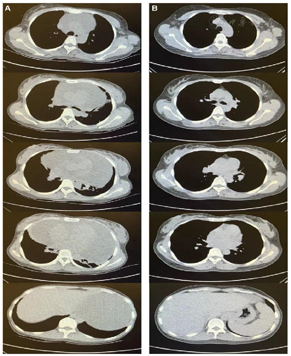

5个月后,患者超声心动及胸部CT提示心包积液完全吸收(图1)。EB病毒:EBV-DNA(血浆) 8.7×102拷贝/ml,EBV-DNA(PBMC)4.9×104拷贝/ml,较前明显下降。目前患者规律信迪利单抗联合来那度胺免疫治疗,无胸闷、憋气等不适。